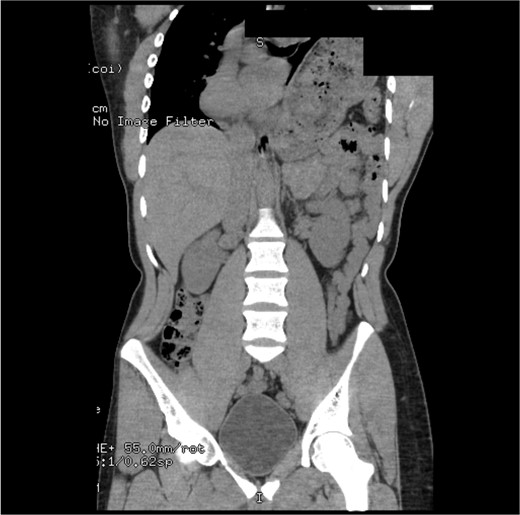

The early postoperative course was unremarkable. The patient reported feeling mild bloating, but was discharged on postoperative Day 1 after removal of a chest tube (Fig. 4). A few hours after discharge from the hospital, he developed dysphagia, progressive abdominal pain, distension, and dyspnea that prompted a return to the hospital. Physical examination revealed tachycardia (132 bpm), mild hypoxia requiring supplemental O2 at 2 L/min via nasal canula, and abdominal distension. Laboratory studies showed WBC of 12 600 cells/μL. A CT scan of the abdomen and pelvis revealed a large, acute organo-axial gastric volvulus without evidence of ischemia, and an intact left hemidiaphragm plication at a similar height to the right hemidiaphragm (Fig. 5). A nasogastric tube was placed with immediate drainage of 1 L of dark bilious fluid with immediate relief of the patient’s symptoms. However, a subsequent film revealed the nasogastric tube projecting toward the upper left chest with presence of colonic haustra (Fig. 6), consistent with acute hemidiaphragm rupture.

CT revealing intact diaphragm plication with massive organo-axial gastric volvulus.